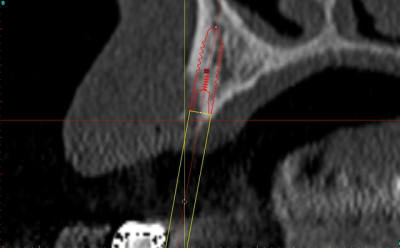

exemple perso, pour la canine, je suis persuadé qu'un guide aurait entrainé un positionnement différent de l'implant(palatin).